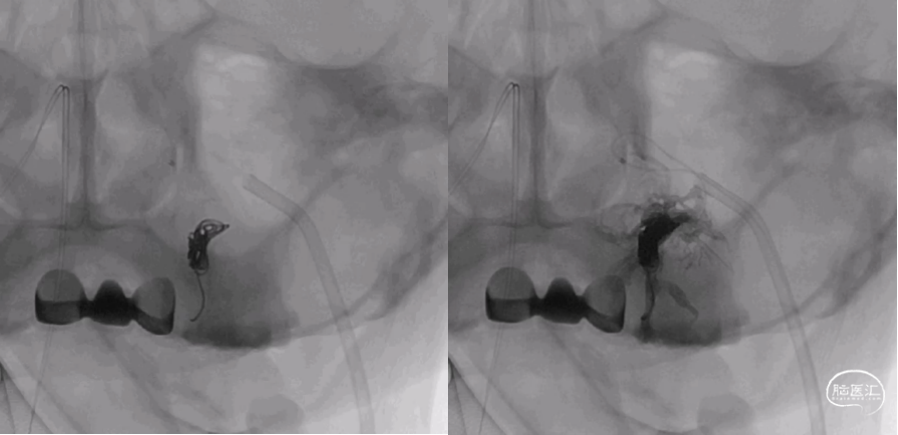

术中将导引导管置于左侧颈内静脉,并引导至左侧岩下窦,Echelon-10微导管经由髁静脉超选至瘘口处。微导管到位后再次进行双容积三维后处理,验证微导管到位位置为术前所判断的瘘口处(图4),随后在瘘口放置一枚弹簧圈,并在阴性路图下注入Onyx胶0.8ml(图5)。复查造影见瘘口完全栓塞,异常引流彻底消除(图6)。